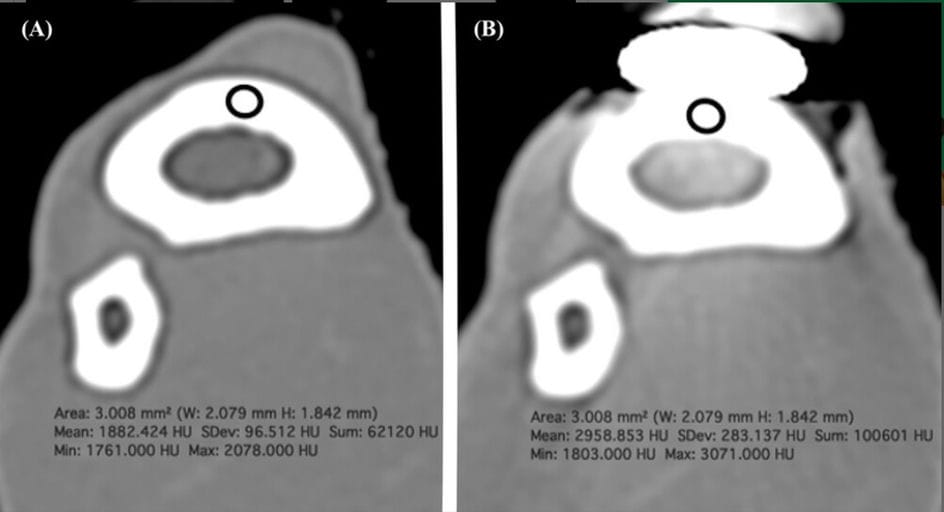

Transverse images pre- (A) and post-implant (B) application, reconstructed with a high-frequency algorithm and displayed with window level = 217 and window width = 1980, showing an example of the difference in Hounsfield units (HU) measurements at the cranial radial cortex (CrC) at Site 2.

Significant HU increases after implant placement were observed in the cranial cortex, radial medulla, and caudal cortex at Sites 2 and 3 (locations directly adjacent to the plate). At Site 1, the cranial cortex showed a significant decrease in HU, while other tissues at that site showed no significant differences. No significant HU changes were observed at Sites 4 or 5, which were 1–3 cm proximal to the implant. Caudal soft tissues showed no significant changes at any site. The results demonstrate that metal implants substantially alter CT attenuation values of adjacent cortical and medullary bone.